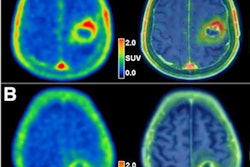

Our second story focuses on a new study conducted at LMU University Hospital in Munich, Germany. The authors found that PET helps clinicians predict survival outcomes for patients with brain tumors, and they published their findings on 3 August in the Journal of Nuclear Medicine.